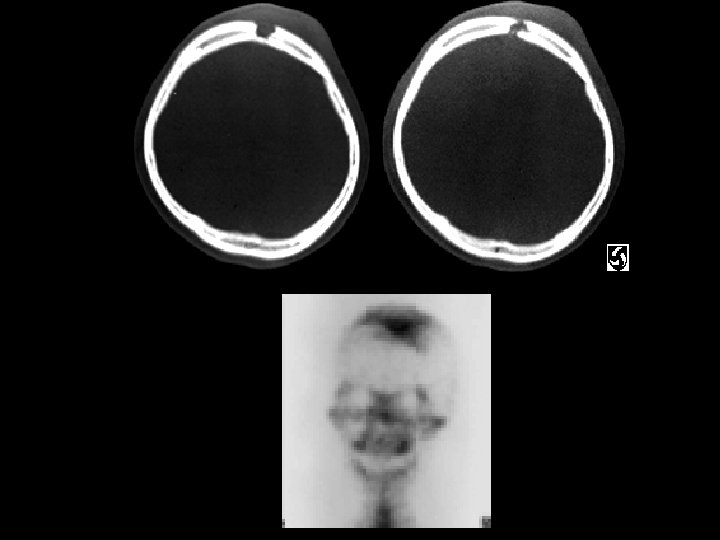

Osteopetrosis • Findings: – generalized increased bone density • rare bone dysplasia • Trabecular --> compact • Anemia w/extramedullary hematopoiesis • ddx: (children) – pyknodysostosis – renal osteodystrophy – vit A, D – Lead – Fluorosis

Eosinophilic Granuloma • Findings: – Well-defined lytic lesion in the frontal skull crossing the diploic space – Overlying scalp swelling – Positive bone scan • ddx: – Osteomyelitis – Metastasis